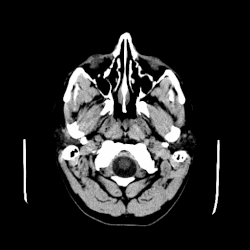

A CT scan of an arachnoid cyst | |

The diagnostic process typically begins with a medical history workup followed by a medical examination by a physician. Imaging tests, such as CT scans and MRIs, help provide a clearer picture. The physician typically looks for fluid (or other bodily substance) filled sacs to appear in the scans, as is shown in the CT scan of a colloid cyst. A primary health care provider will refer an individual to a neurologist or neurosurgeon for further examination. Other diagnostic methods include radiological examinations and macroscopic examinations. After a diagnosis has been made, immunohistochemistry may be used to differentiate between epithelial cysts and arachnoid cysts.[2] These examinations are useful to get a general idea of possible treatment options, but can be unsatisfactory to diagnose CNS cysts.[3][5] Professionals still do not fully understand how cysts form; however, analyzing the walls of different cyst types, using electron microscopes and light microscopes, has proven to be the best diagnostic tool. This has led to more accurate cyst classification and correct course of action for treatments that are cyst specific. In the past, before imaging scans or tests were available, medical professionals could only diagnose cysts via exploratory surgery.[2]